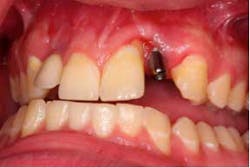

Three days before he left, the patient presented for treatment, the No. 7 implant had been removed, and the site had been grafted, along with No. 10 implant being submerged. A modified lingual veneer preparation was made on the adjacent teeth. The lingual prep served two purposes, the first to increase surface area for bonding and the second to increase the connector cross-sectional area. The ideal cross-sectional area is 16 mm² (*).

The preps were scanned, along with a bite registration, opposing dentition, and the diagnostic wax-up for cloning. The restorations were designed and milled from monolithic e.max HT blocks. The restorations were stained, glazed, and crystalized to final shade and luster.

The restorations were etched with phosphoric acid, cleaned with Ivoclean (*), and bonded with universal bond (*). The preparations were isolated (isolation was very difficult in the area of No. 7 due to surgery the day before), etched, bonded, and the restorations were cemented. Special attention was paid to the occlusion on the FPDs, and all occlusal contact was removed from the connector area. Also, all anterior guidance was removed from the FPDs. The opposing dentition was reshaped to gain as ideal of a contact on the restorations as possible. The patient returned one prior to his leaving to verify his occlusion and post-treatment photographs. At this time, the patient was instructed about hygiene for the restoration and how to carefully function with the restorations. He seemed to be pleased with the functionality and esthetics of the restorations.